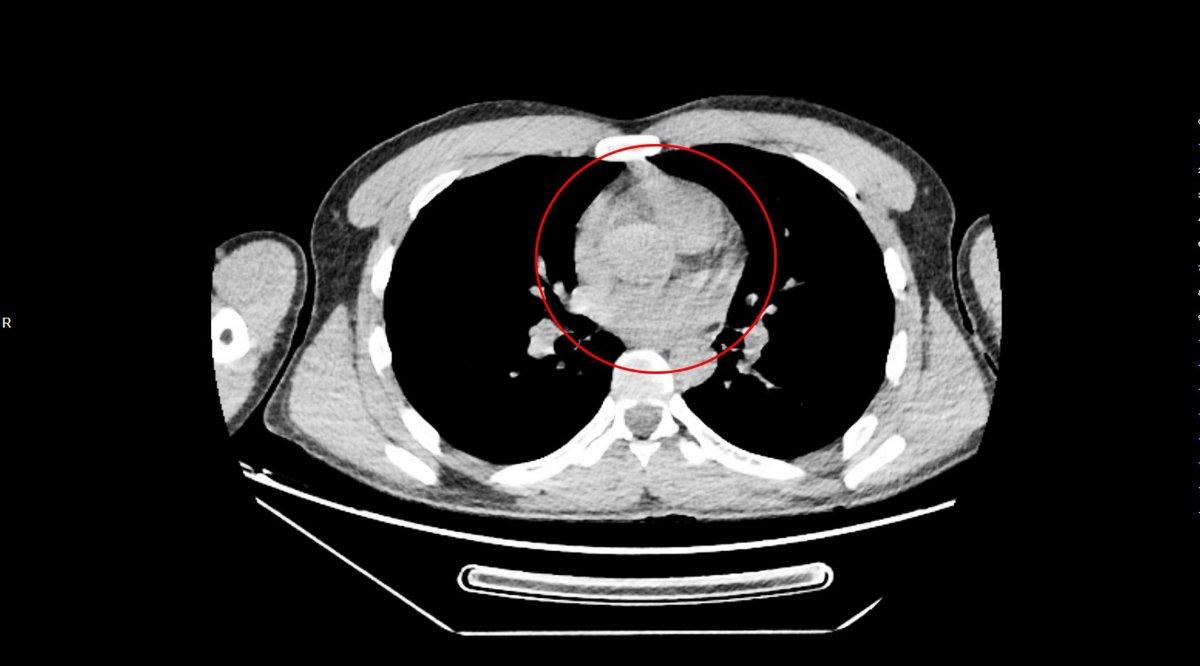

2'Sİ PATLAMIŞ 72 KAPSÜL ÇIKARILDI

Tedavi altına alınan Narziveh'in çekilen röntgen filminde midesinde cisim tespit edildi. Ameliyata alınan Zarziveh'in midesinden 2'si patlamış 72 adet kapsül halinde uyuşturucu madde çıkarıldı.